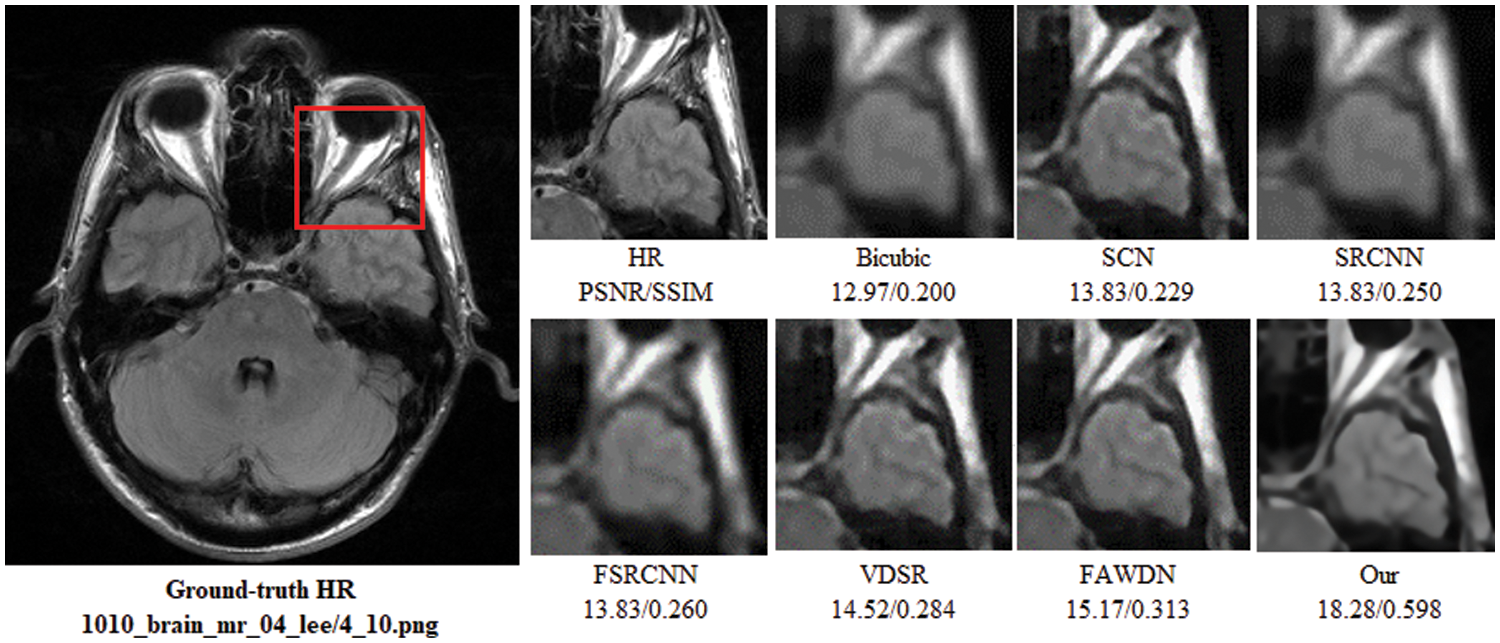

To evaluate the comparison quality of image SR methods with the proposed approach, particularly Bicubic, A+, SelfExSR, RFL, SRCNN, FSRCNN, VDSR, DRCN, LapSRN, DRRN, and IDN techniques. Table 2 presents the quantitative results of different algorithms on the Set5, Set14, BSDS100, and Urban100 test data sets, with an enlargement factor of 2×, 3×, and 4× accordingly. Fig. 6 shows the quantitative performance of state-of-the-art approaches in terms of PSNR vs. network parameters. Our proposed model (IRMRIS) has fewer parameters than the VDSR, DRCN, and LapSRN. Despite having a lower footprint as compared to CNN-based approaches, the performance of the proposed model was demonstrated to be state-of-the-art. As compared to the Bicubic, A+, SelfExSR, RFL, SRCNN, FSRCNN, VDSR, DRCN, and LapSRN. Furthermore, our IRMRIS model has about 1.87, 0.78, 0.79, 0.86, 0.67, 0.56, 0.56, 0.29, and 0.27 dB improvement on the BSDS100 dataset for enlargement factor 3× image SR. Figs. 7–10 present a visual performance comparison of the brain MRI images at enlargement factor 4× SR. The result of the baseline method (bicubic) and SRCNN clearly shows blurry MRI image, but our proposed IRMRIS reconstruct the best results as compared to another state-of-the-art methods MRI image SR.

Figure 9: Perceptual quality comparison of our method with other deep learning-based methods using MRI images at 4× super-resolution. The image is obtained from “1010_brain_mr_04_lee/4_10.png” dataset